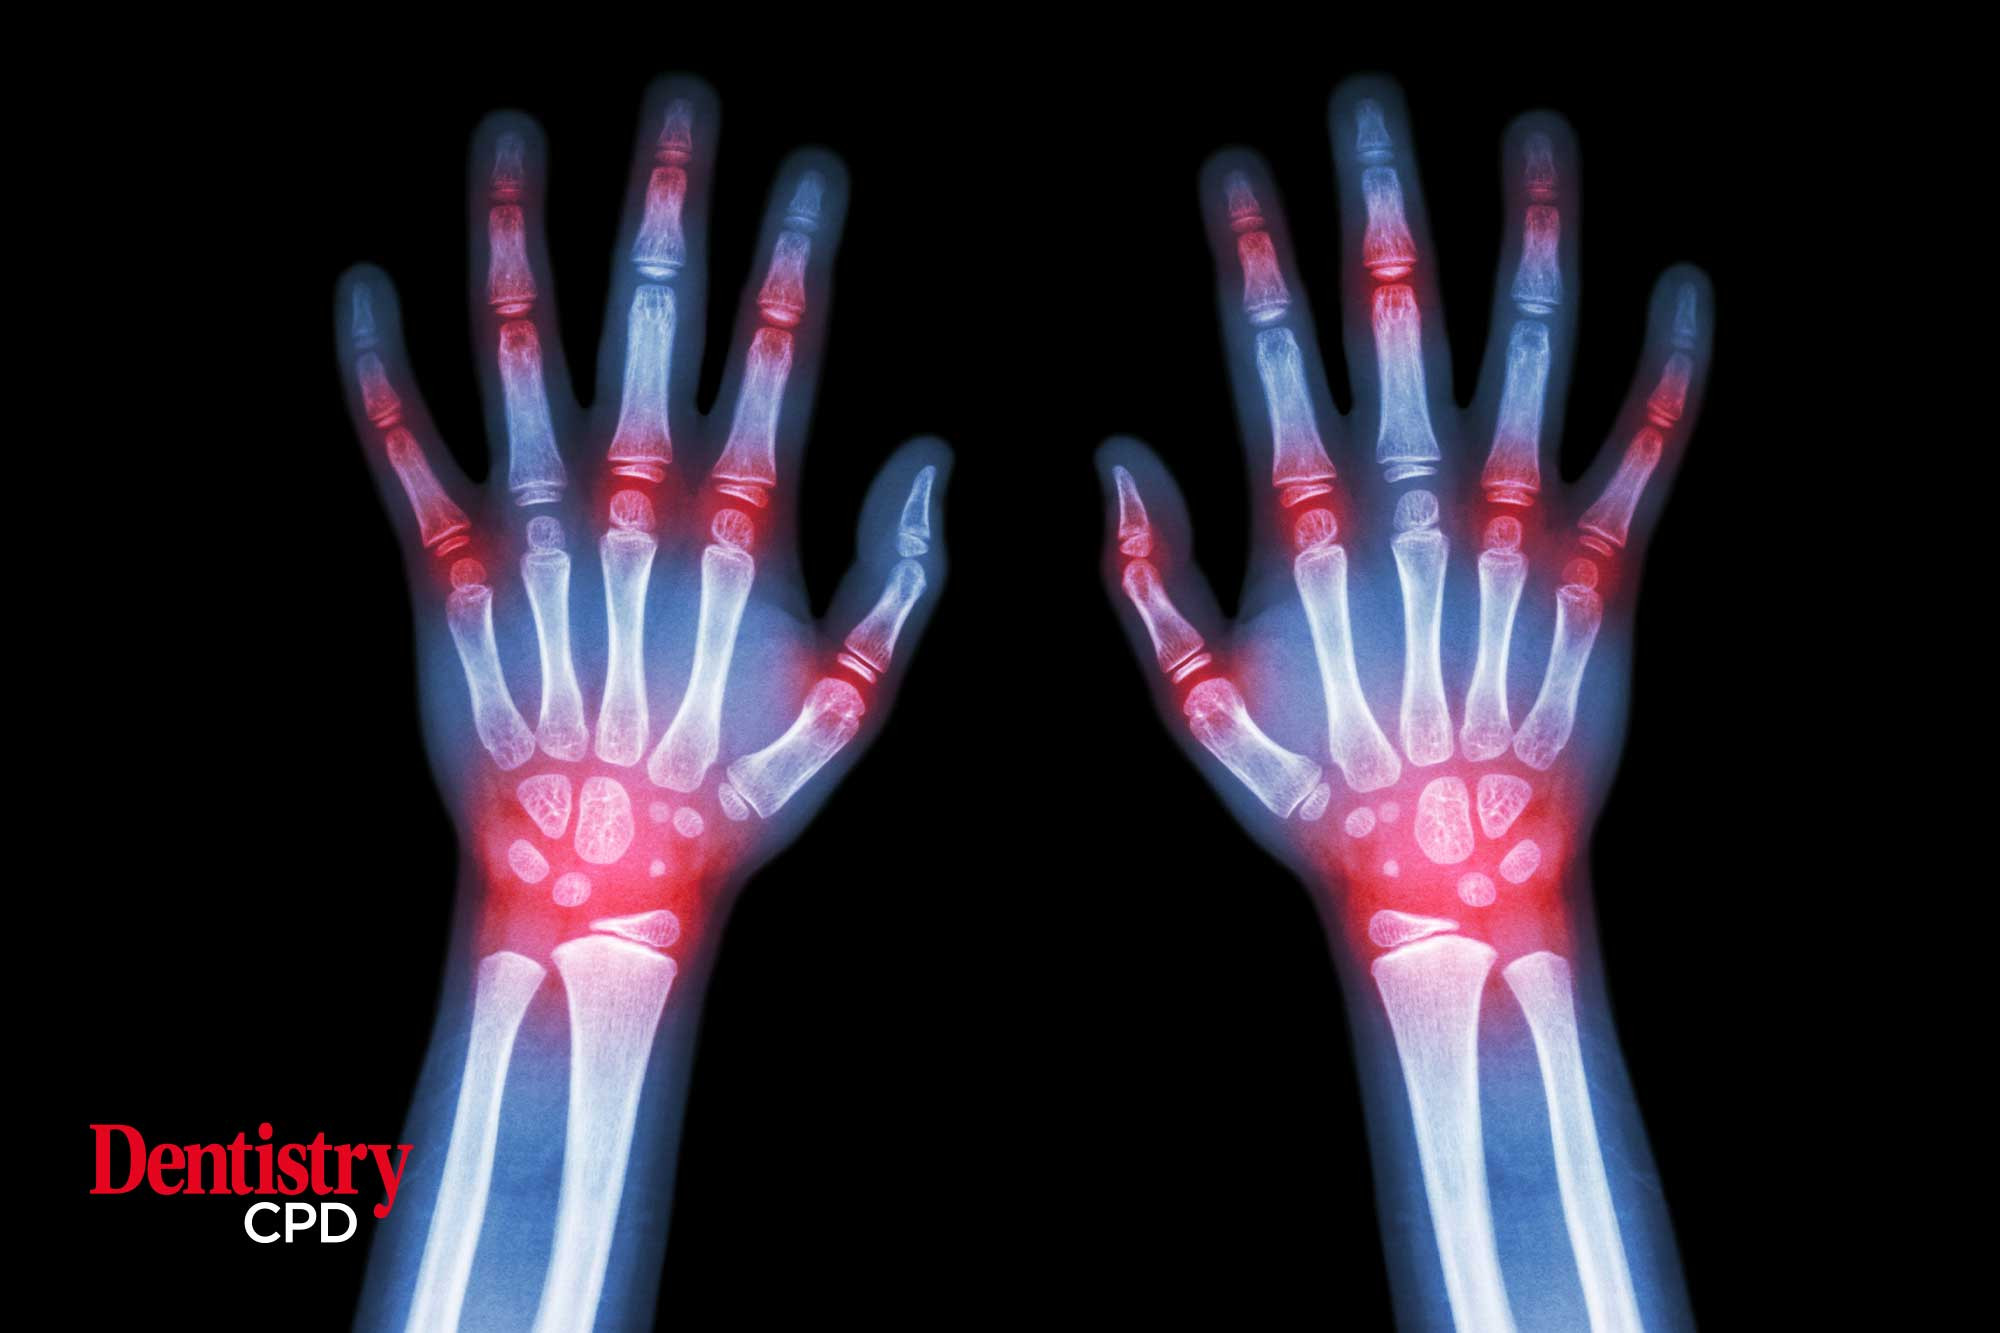

In focus: paediatric rheumatology

Bernie Ffrench examines what dental professionals need to know about paediatric rheumatology.